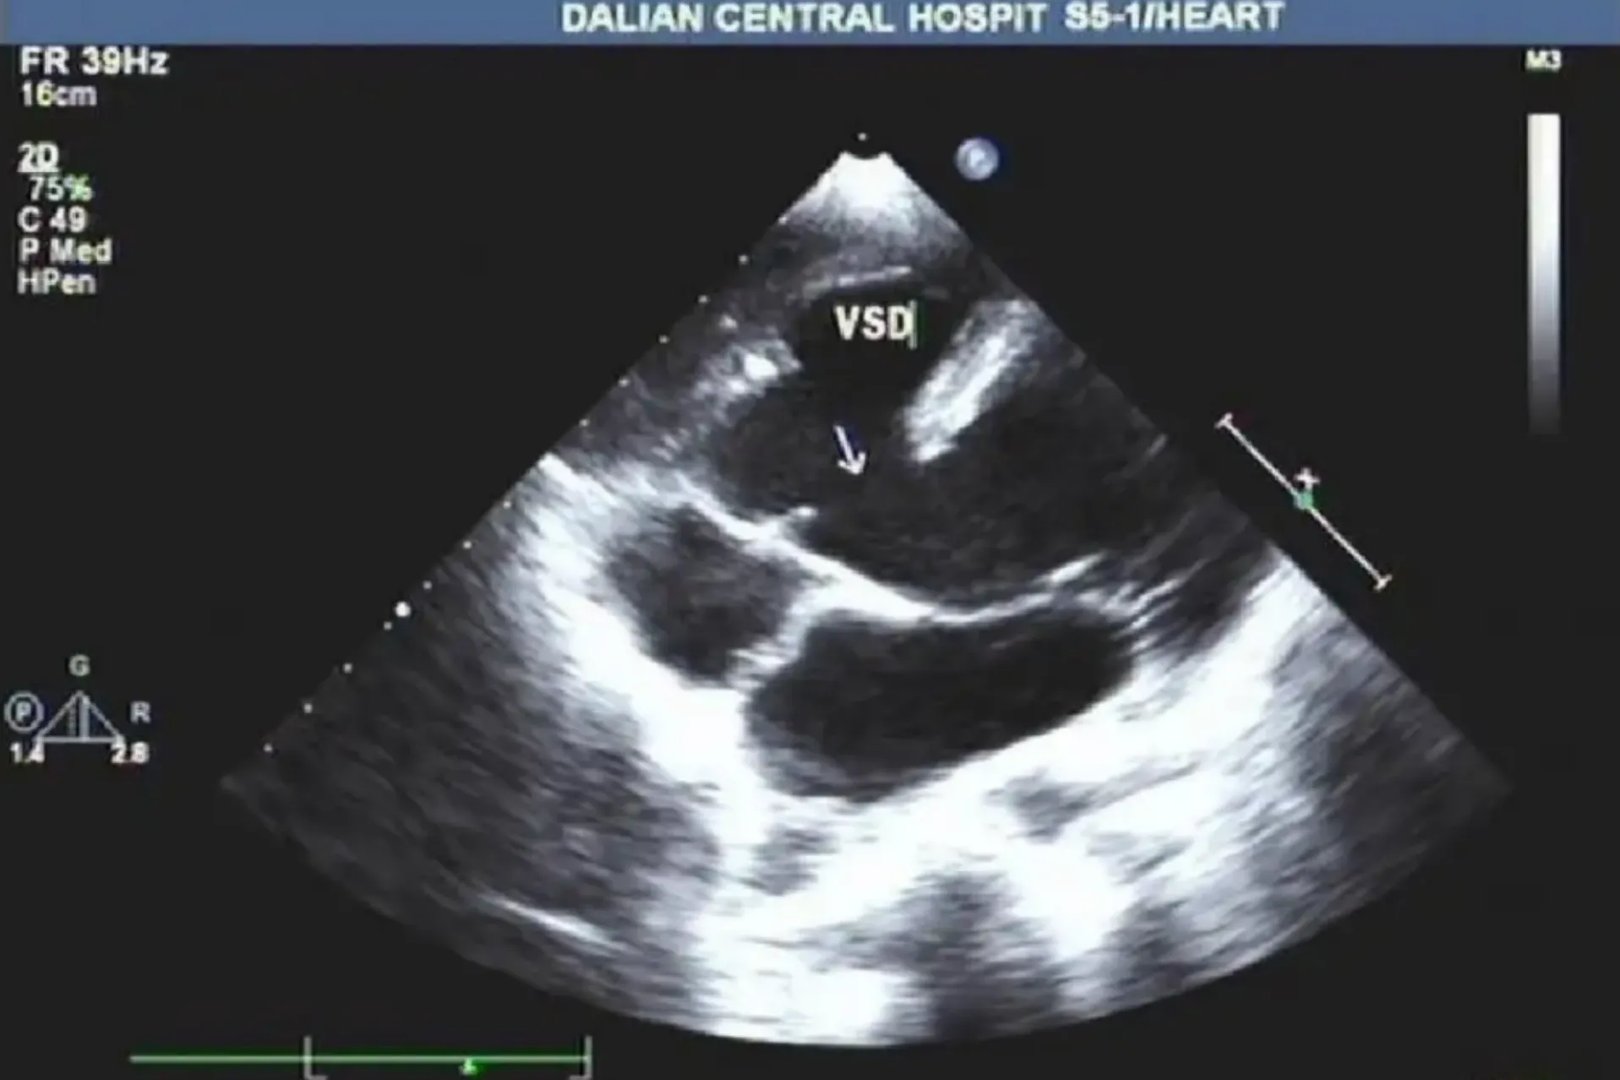

的有关信息介绍如下:彩超是彩色多普勒超声的简称,可对血管、腹腔脏器、心脏、子宫及附件、小器官、前列腺及精囊等全身性脏器进行检查。